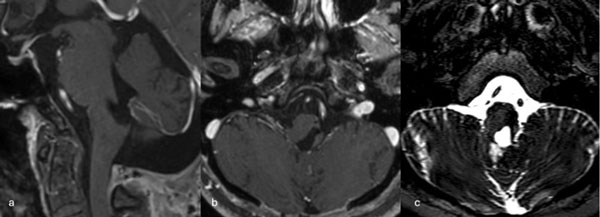

Figura 6. RM preoperatoria de encéfalo. Se evidencia una lesión única intraaxial localizada en el puente y pedúnculo cerebeloso medio izquierdo, hiperintensa en T1 y con un anillo hipointenso en T2, característica de una malformación cavernomatosa con sangrado reciente. A) Imagen ponderada en T1 en corte sagital. B y C) Imágenes ponderadas en T2 en cortes axial y coronal, respectivamente.

Figura 7. Imágenes intraoperatorias bajo microscopía. Abordaje retrosigmoideo ampliado a izquierda, con ruta de ingreso transpedúnculo cerebeloso medio. A) Apertura de fisura horizontal que divide los lóbulos semilunar superior y semilunar inferior del cerebelo, exponiendo el pedúnculo cerebeloso medio. B) Corticotomía en pedúnculo cerebeloso medio, evidenciando la cápsula del cavernoma. C) Resección en bloque de la malformación cavernomatosa. D) Revisión del lecho, sin remanente.